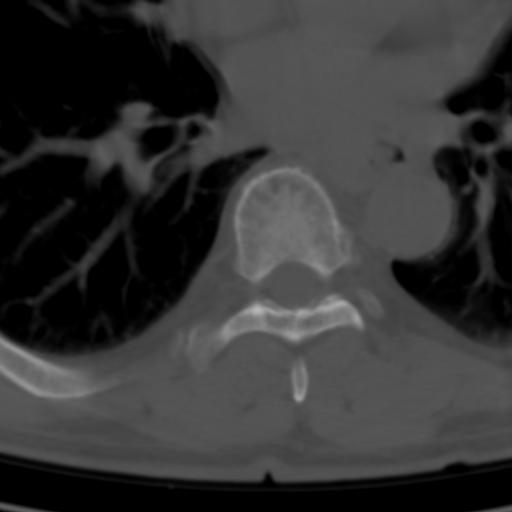

标题: CT25189:胸椎ct,请会诊!

既往食管癌,现行ct检查!

仅见椎体退行性改变

中上段食道癌,椎体轻度退变。

椎体退行性改变,食管癌。

支持中上段食道癌,椎体轻度退变,必要时做ect。

支持中上段食道癌,椎体轻度退变。